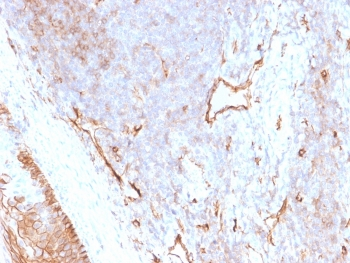

IHC staining of FFPE human prostate carcinoma with CD73 antibody (clone NT5E/2545). HIER: boil tissue sections in pH9 10mM Tris with 1mM EDTA for 10-20 min and allow to cool before testing.

IHC staining of FFPE human pancreatic carcinoma with CD73 antibody (clone NT5E/2545). HIER: boil tissue sections in pH9 10mM Tris with 1mM EDTA for 10-20 min and allow to cool before testing.